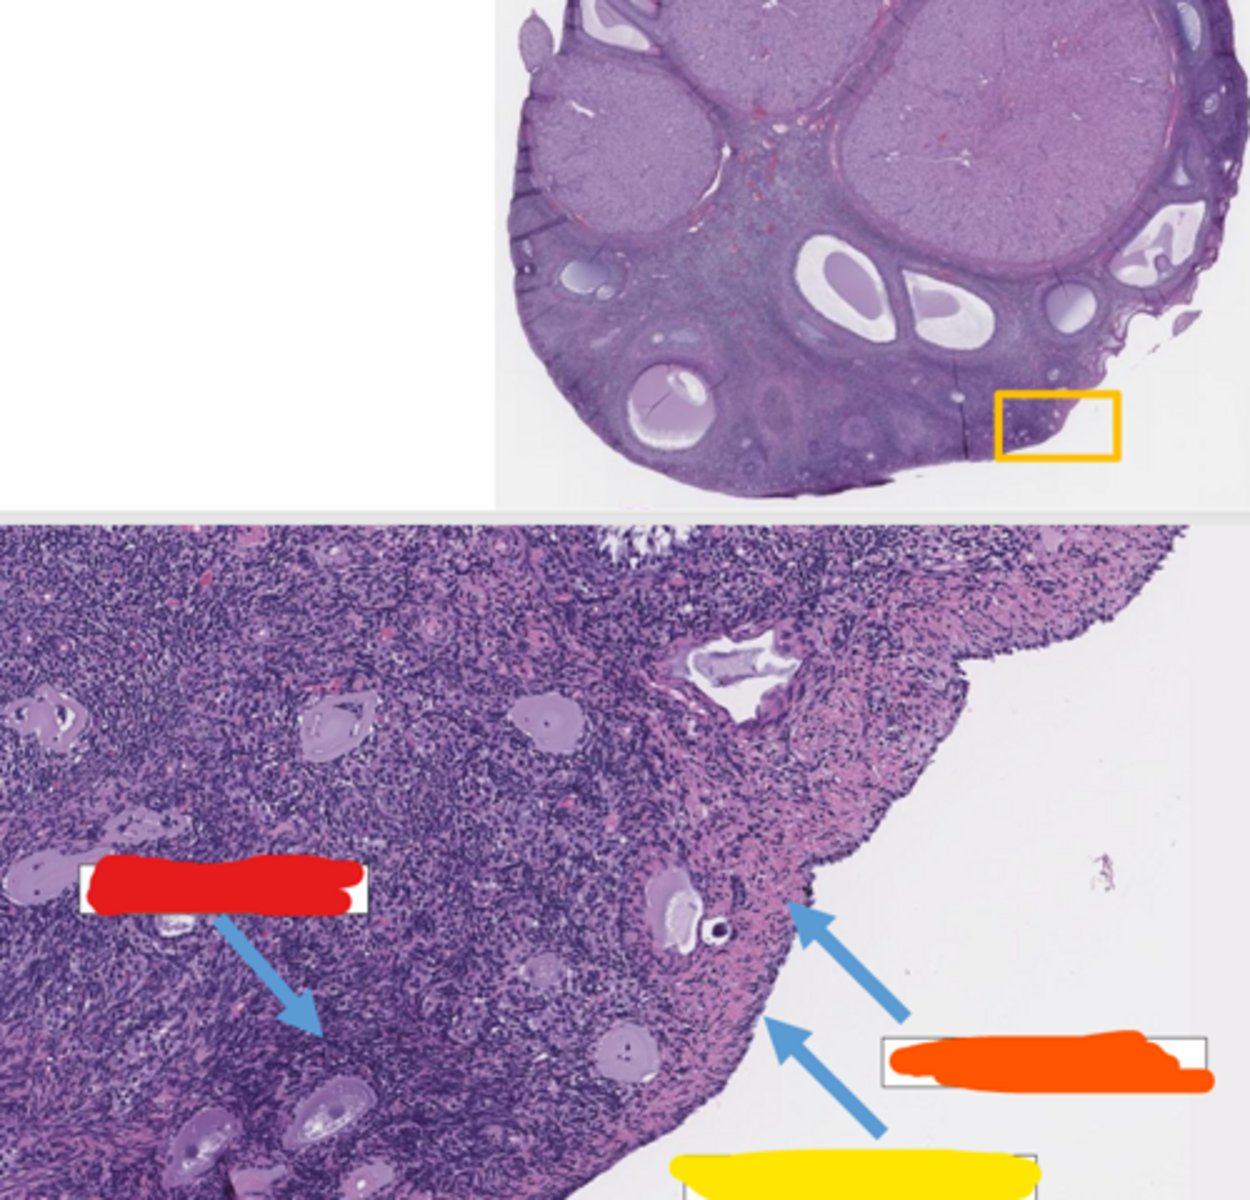

corpus hemorrhagicum

ruptured follicle filled with hemorrhage

ovulatory papilla

The _____ is the small, nipple-like protrusion on the ovarian surface marking the site where the follicle ruptured, which subsequently fills with blood to form the corpus hemorrhagicum.

luteum

the corpus hemorrhagicum becomes the corpus _____

the process of granulosa and thecal cells collapsing into the ruptured follicle and undergoing hypertrophy and hyperplasia

granulosa and thecal cells

what collapses into the ruptured follicle (corpus hemorrhagicum) and gets hypertrophied and has hyperplasia?